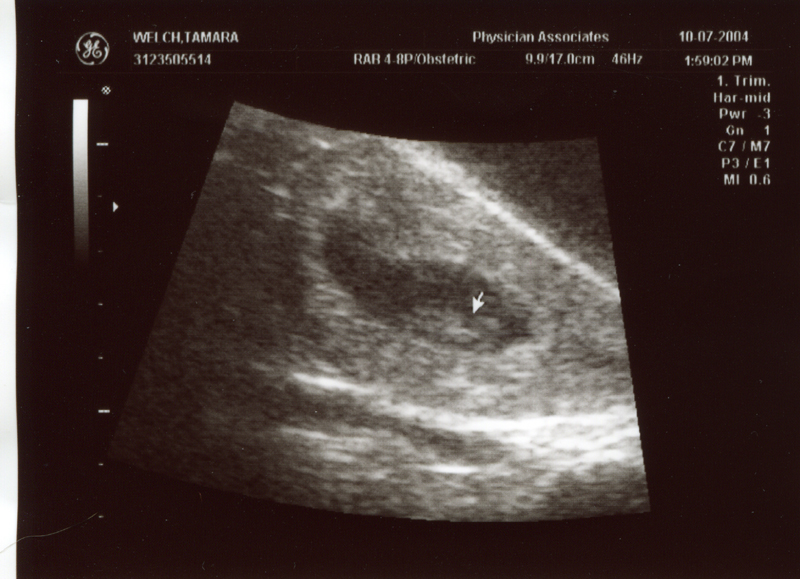

October 7, 2004 - We had

our first ultrasound of the baby! The heartbeat is 161 bpm and

it's 3 cm long. Click on the images below to see the pictures

from the ultrasound.